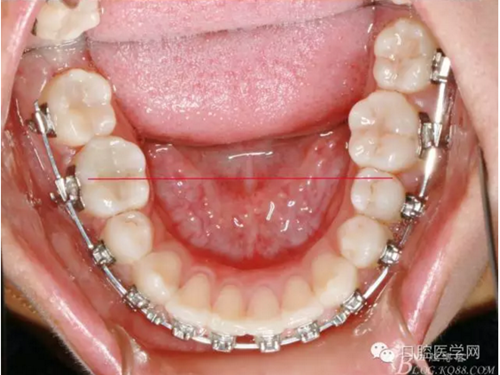

正畸醫(yī)生都想把患者做到“理想頜”,而臨床工作中卻很難如愿;這個(gè)患者到診時(shí),口內(nèi)已經(jīng)有兩顆恒牙缺失;

37,45缺失后,鄰牙近中移動(dòng)占據(jù)了部分牙位;患者要求減少治療費(fèi)用,不做種植修復(fù),那怎么協(xié)調(diào)右側(cè)的咬合關(guān)系?

15是根管治療過(guò)的牙齒,只好忍痛舍去......

在滿足功能的前提下,退而求其次...有時(shí)候,正畸醫(yī)生不得不妥協(xié)。